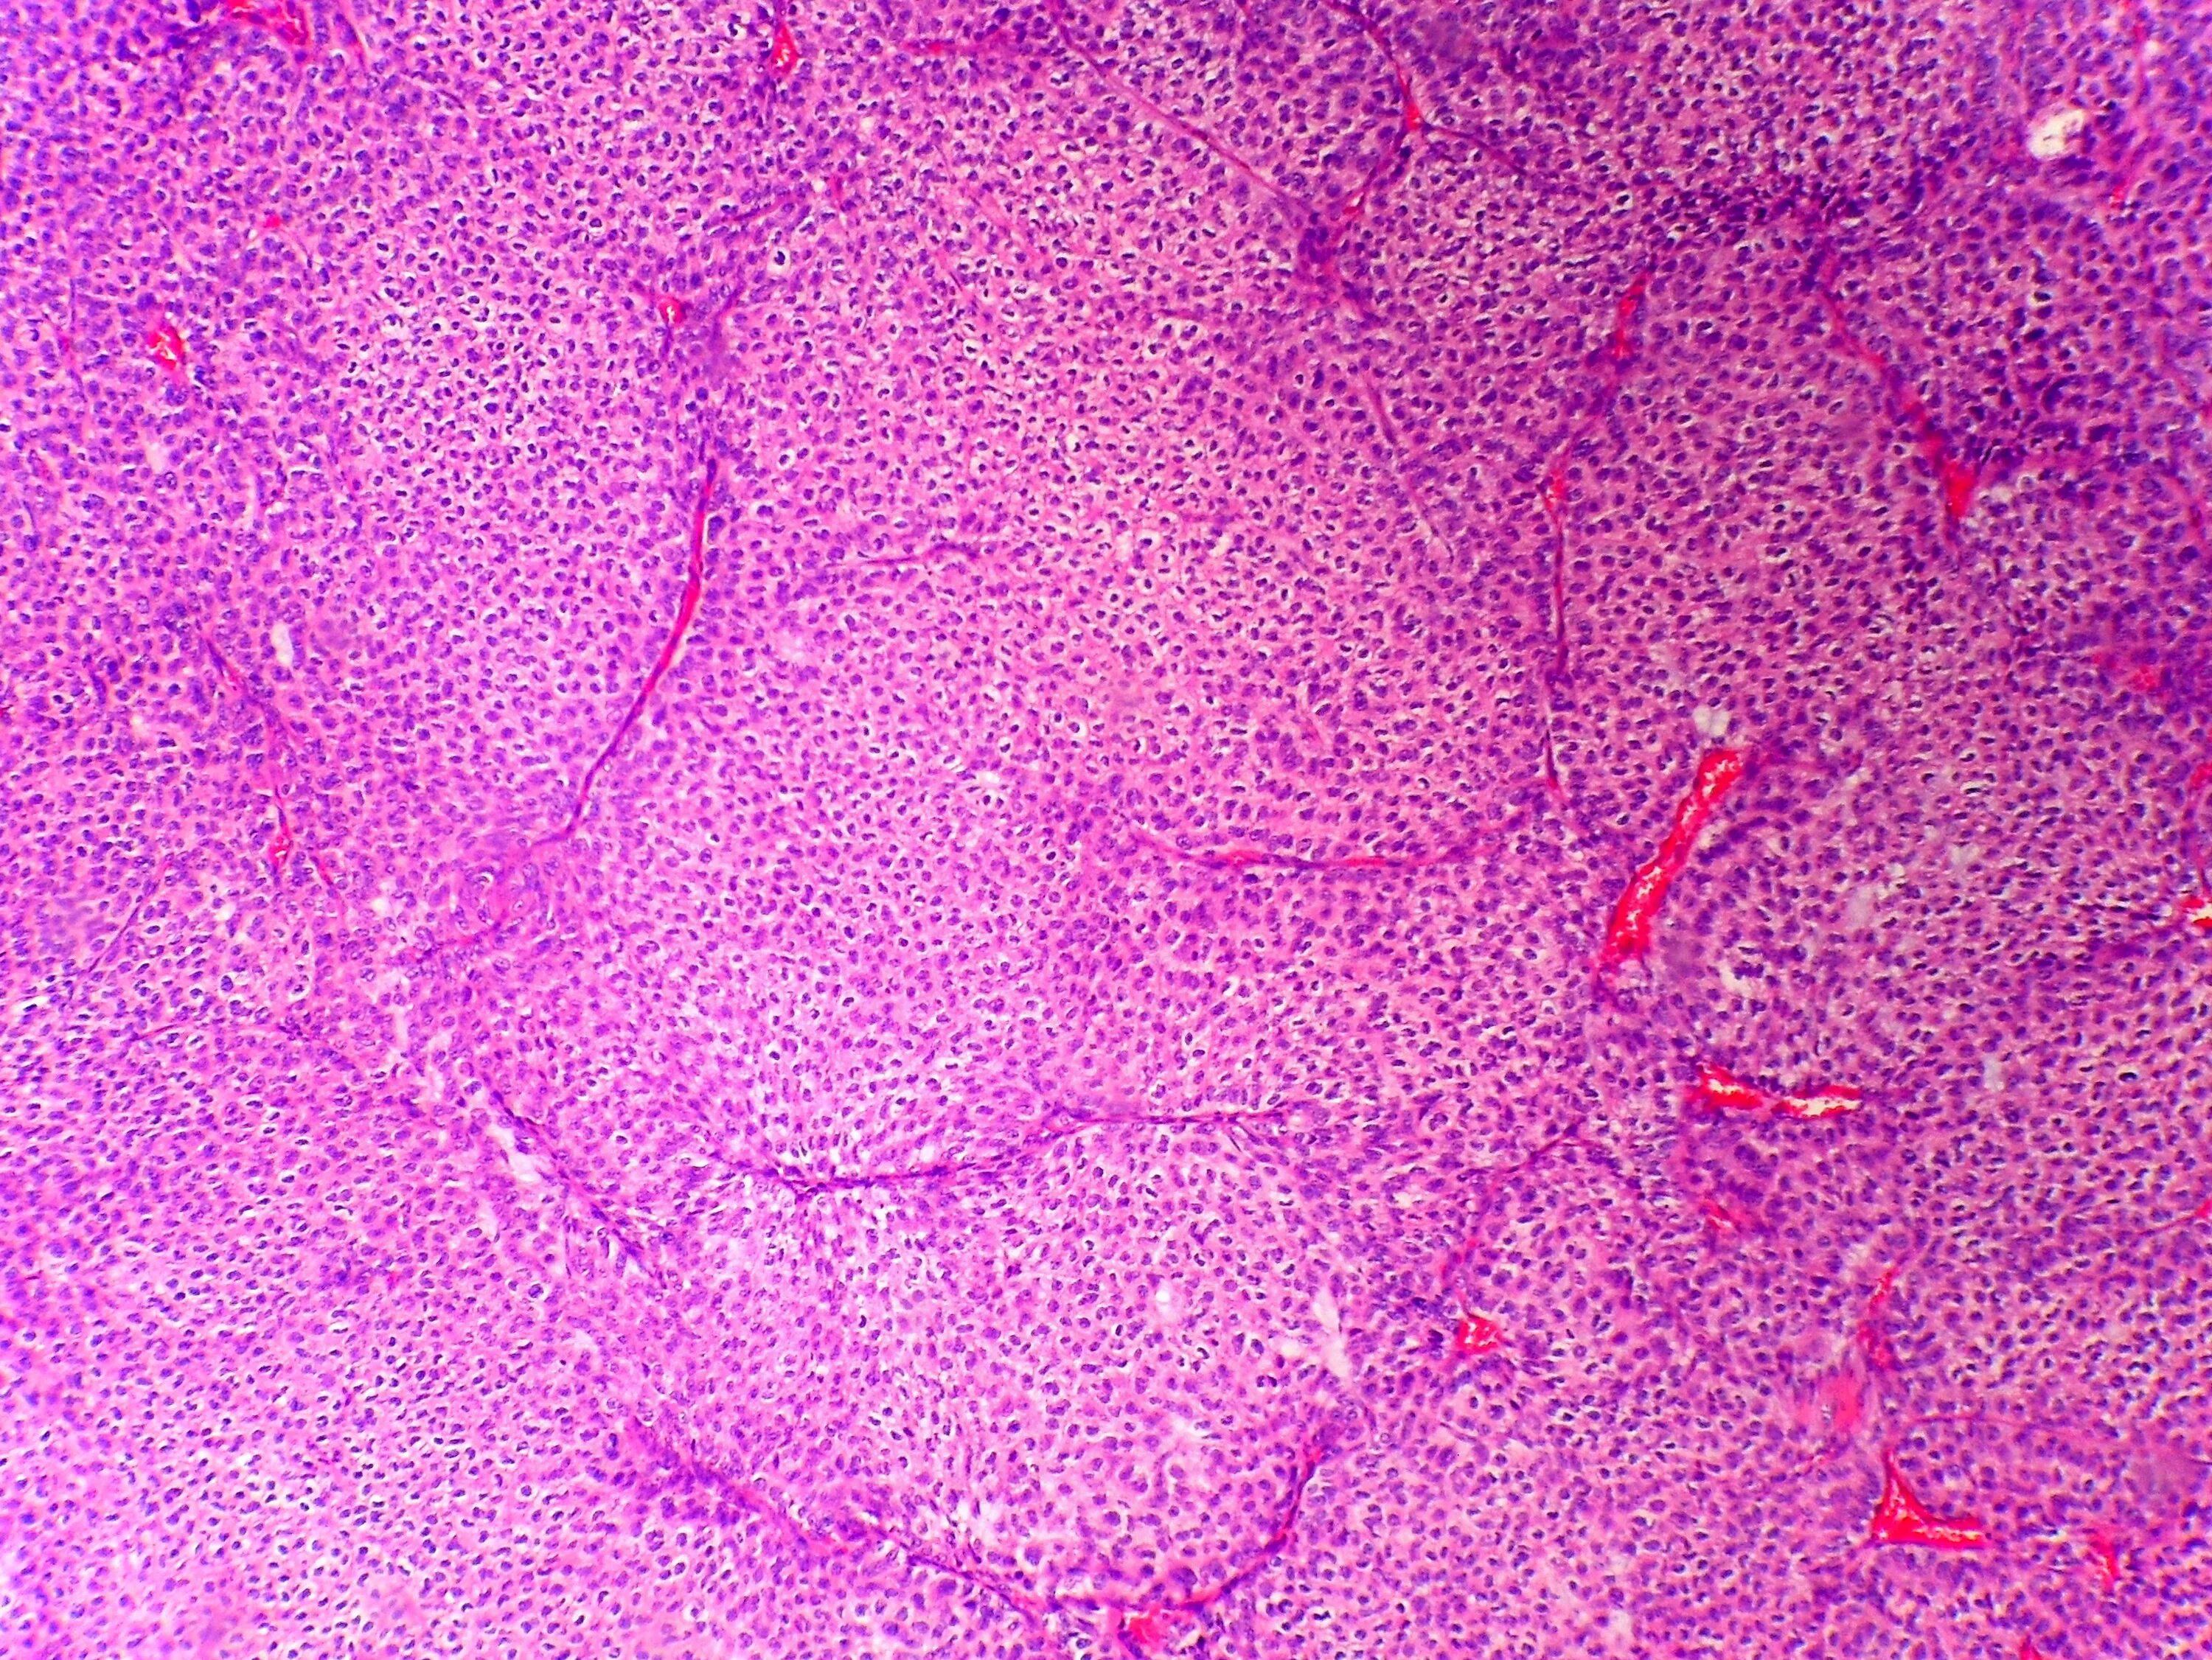

Гистология фото